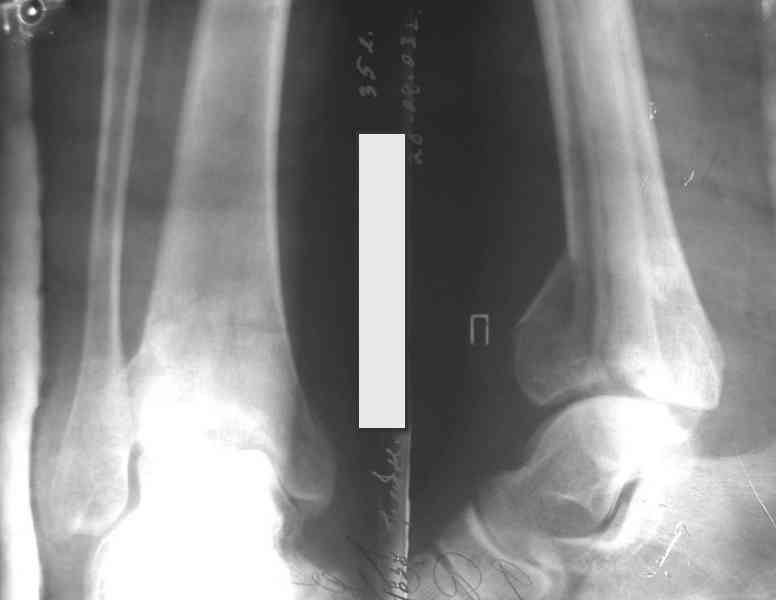

На рентгенограммах типичный перелом пилона по типу С-3. есть опыт до 100 открытых опреаций у нас в клинике. 20 примерно в год. Принцип один -все внутрисуставные переломы нуждаются в открытой репозиции и внутренней стабильной фиксации. При поступлении КТ не надо, так как получается только нагромождение костей. Истинной картины нет. Главное восстановить длину малоберцовой кости - это ключ к успеху. При поступлении меньше всего надо думать о сосудистых расстройствах, т.к. сама операция и репозиция даже сначала частичная даёт улучшение сосудитых нарушений. Причём очень быстро. Операция в 2этапа. При поступлении доступ позади наружной лодыжки, причём обязательно. После этого репозиция малоберцовой кости и фиксация пластиной 1/3 трубки под винт 3,5. Дренаж и любой аппарат наружной фиксации. Затем после спадения отёка на 5-7-10 день аппрат снимается и дугообразный разрез спереди от медиальной лодыжки 10-12 см. Главной чтобы расстояние между 1 и вторым разрезом было не меньше 7-8 см. Тогда не будет некрозов лоскутов. Таранная кость используется как матрица на неё укладываются отломки и фиксируются пицами. Ренг-контроль. Отломки лежат все отдельно, но ничего не высыпется. При переломах С-3 всегда нужна костная пластика (из крыла). Фиксация пластиной лист клевера простой или LCP. Гипс не нужен. Дренаж до 48 часов. Операция длится 3-4 часа обязательно без жгута. Посылаю примерно такой же случай.